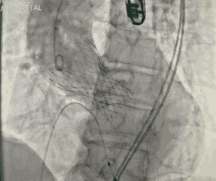

葛均波院士、周达新教授结构团队对这位生物瓣衰败的老年男性患者行瓣中瓣植入术,术中选择了23mm VenusA-Valve(杭州启明),植入过程顺利,术后冠脉无堵塞,未出现瓣周漏,术后跨瓣压差接近于0,赢得了参会专家的激烈掌声。

此患者是我国第一例接受TAVR患者,十年后再次接受TAVR,并获得完美结果,意义重大。本病例也是我国第一例TAVR瓣膜衰败患者再次TAVR手术的病例。

本病例的成功也为目前接受TAVR患者远期瓣膜衰败问题的解决提供良好借鉴,为这些患者解除后顾之忧。

图5 TAVR瓣膜释放后